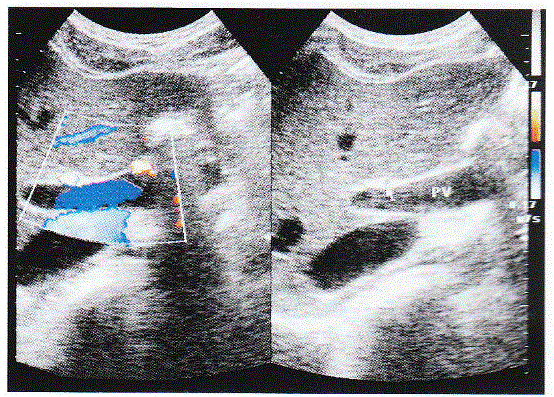

问题 下列彩图是肝脏正常超声图像,请回答箭头所指部位的解剖名称:

选项 A.肝动脉 B.肝静脉 C.胆总管 D.门脉主干

答案 A